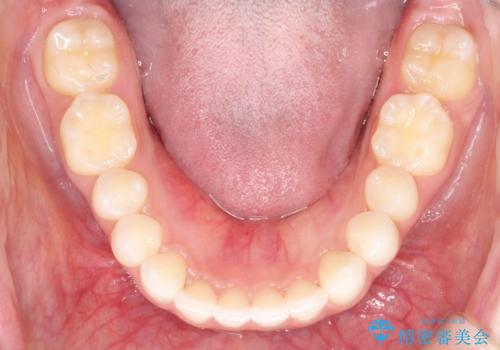

出っ歯の矯正治療 歯を抜かずにインビザラインで

- インビザラインで出っ歯を治したいとの希望がありました。

上顎の歯を全体的に後方に移動させて前歯を引っ込める計画としました。

インビザラインで目立たずに、痛みも少なく矯正治療を終えることができ満足していただけました。